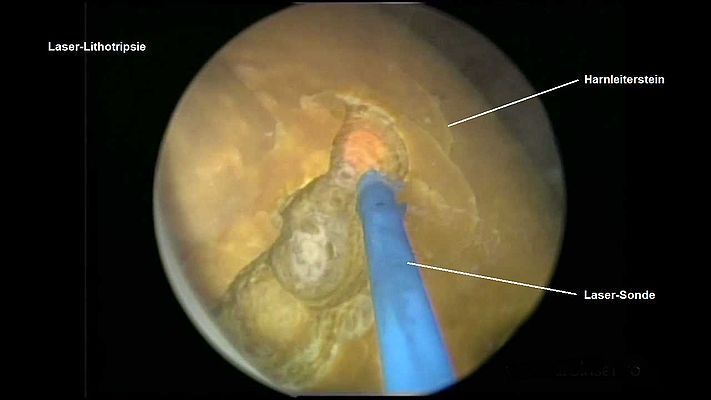

Wie die Humanmedizin ist auch die Tiermedizin heute weit fortgeschritten: Das Problem der Harnleitersteine wurde in der Vergangenheit mittels Laser-Lithotripsie (hierbei wird ein Katheter via Harnröhre und Blase in die Harnleiter vorgeschoben und der blockierende Stein mittels Laser zertrümmert) und Harnleiter-Stents (ein Röhrchen, welches endoskopisch in den Harnleiter eingeführt wird und diesen erweitert, damit Urin abfliessen kann) angegangen. Offenbar sind die Nebenwirkungen dieser Methode aber nicht zu unterschätzen, weshalb heute v.A. das SUB-System zur Anwendung kommt. Wenn auch der Eingriff für die Katze und die Besitzerin eine grosse Belastung dargestellt hat, gibt der Erfolg dem Entscheid zur Operation recht - Manolo kann heute wieder ein normales, unbelastetes Leben führen.